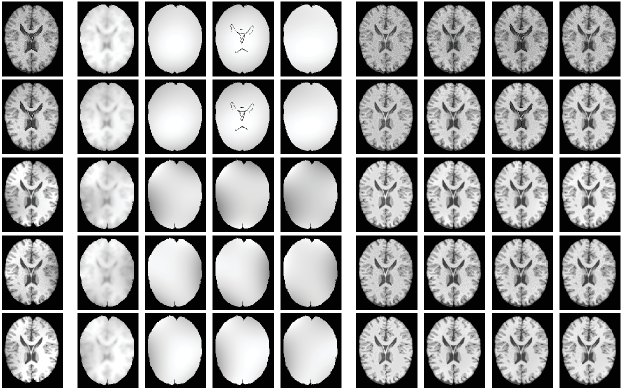

4.2 Evaluation on pubic image repositories

In this subsection, we evaluate effectiveness of the proposed model quantitatively on one simulated MR dataset and one real MR image dataset. The first one consists of 9 cases of MR images with three different levels of noise and intensity inhomogeneity, respectively. Resolutions of the images are with 1 mm in-plane pixel size and 1 mm slice thickness. For more information about the dataset, interested readers are referred to the website http://brainweb.bic.mni.mcgill.ca/brainweb/ and the reference [33]. To construct a much more challenging dataset for segmentation methods, three more levels of non-linear intensity inhomogeneities are added to the original image with noises. Therefore, there are totally 18 image cases for the first image dataset. The second image set is known worldwide as the Internet Brain Segmentation Repository (IBSR) which contains 18 cases of T1-weighted brain MR image cases with skull-removed masks and manually-guided expert segmentation results. Resolutions of the images are all . Interested readers are referred to https://www.nitrc.org/projects/ibsr for detail. Note that for each image case, the segmentation task is to extract white matter (WM), gray matter (GM), and cerebrospinal fluid (CSF) from the background. As intensities of the background are all zero for the images, two level set functions are used to partition the images into three regions that is and . To compare performance of the proposed model with state-of-the-art models like CV, LIC, and LINC on these image datasets, we first extend the comparable models to three phase (matlab codes will be released on our personal homepage if this paper got published). We then define membership functions , , and to represent WM, GM, and CSF, respectively. For a fair comparison, we first extend comparison models to three phase and then use the same parameter set and the same strategy to initialize the level set functions for all the comparison models. The initialization strategy is that areas separated by a predefined threshold are adopted to initialize by considering the areas as inside and outside of the zero level contour. Areas separated by another predefined threshold are adopted to initialize the level set function . The thresholds are adaptively defined as 0.8 and 0.3 times of maximal intensity of pending to be segmented images. We have to point out that the proposed model is robust to initialization which will be discussed in section 5.3. Note that we applied the proposed model and comparable state-of-the-art models only on image slices that really contain WM, GM, and CSF.

4.2.1 Qualitative comparison

Segmentation results of the proposed model with three state-of-the-art level set models, i.e., CV, LIC, and LINC, and the global clustering based MICO on the -th slice of selected brainweb cases and the -th slice of selected IBSR image cases are given in Fig. 8 and Fig. 10. The corresponding bias estimation and correction results are given in Fig. 9 and Fig. 11, respectively. The reason we select these image is that they are the most noisy and biased and they are therefore challengeable. It can be seen that 1) the proposed model is much more robust to noises and bias fields and 2) segmentation results of the proposed model are much more close to corresponding ground truth. Due to potential relatedness of the proposed model to MICO, it is necessary to compare them qualitatively and quantitatively, beside describing theoretical differences as given in Remarks 8-10. It can be obviously seen that 1) MICO is sensitive to noise, especially as shown for the first two images of Fig. 8 with 9% and 6% noises to the brightest tissue and 2) MICO prefers to provide high biases at image centres which can be seen from Fig. 10 and especially for the first image in Fig. 8 with no intensity biases actually. But bias fields estimated by the proposed model are much more matching with the actual situation and the bias estimated is almost a constant for the first image in Fig. 8 which is not corrupted by inhomogeneities in fact. Quantitative evaluation will be given in section 4.2.2.

Orig Bias Corrected

LIC LINC MICO IEOPF LIC LINC MICO IEOPF